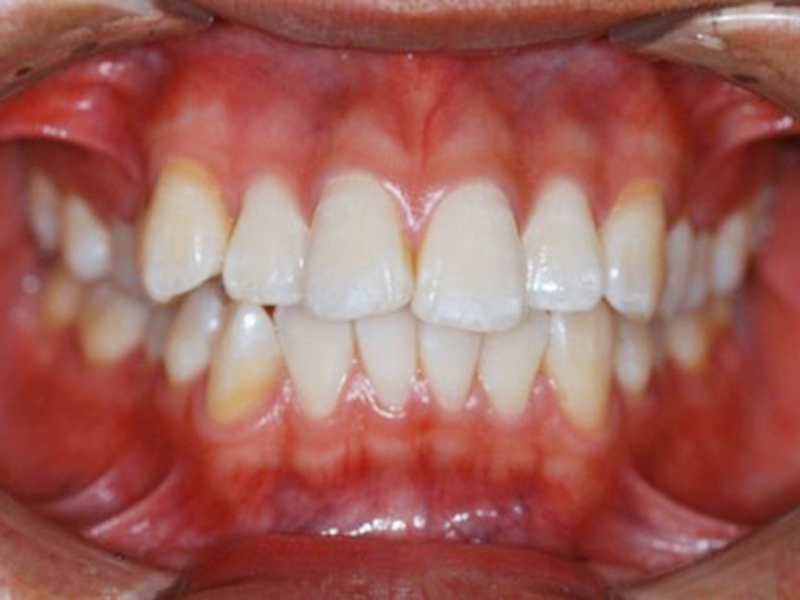

▼ ケース5 下顎前歯部叢生症例

治療終了時